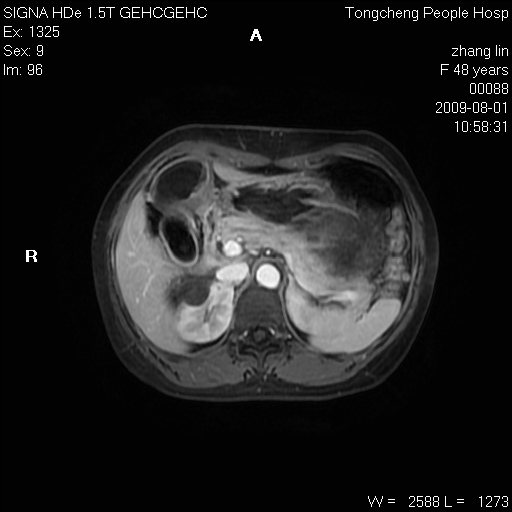

女,48岁。健康体检,彩超发现右肾占位性病变。平素健康。

临床诊断:右肾占位性病变,性质待定(囊肿?肿瘤?)。

上中腹部mr平扫+增强扫描,图像如下:

右肾上极见一类圆形病灶,t1wi呈等信号t2wi呈等高混杂信号,三期增强无强化,边界清---考虑囊肿出血。

同反相位均表现为等信号,病变无强化,考虑含蛋白的囊肿可能,弥散加权相或许有些帮助,